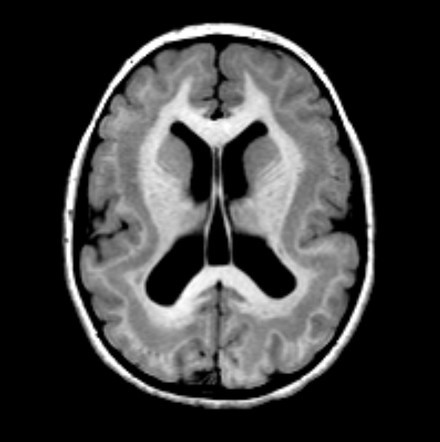

Lissencephaly

Diagnosis of lissencephaly